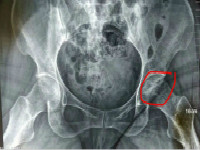

股骨头坏死是一种较为严重的骨科疾病,患上股骨头坏死以后很多患者并不了解股骨头坏死分为哪些类型,文章为您解读股骨头坏死的几种常见的类型。

股骨头坏死目前引起了大多数人的重视,患上此疾病的患者并不是十分了解股骨头坏死的分期。对股骨头坏死不了解在治疗的过程中就有可能存在一定的误区。